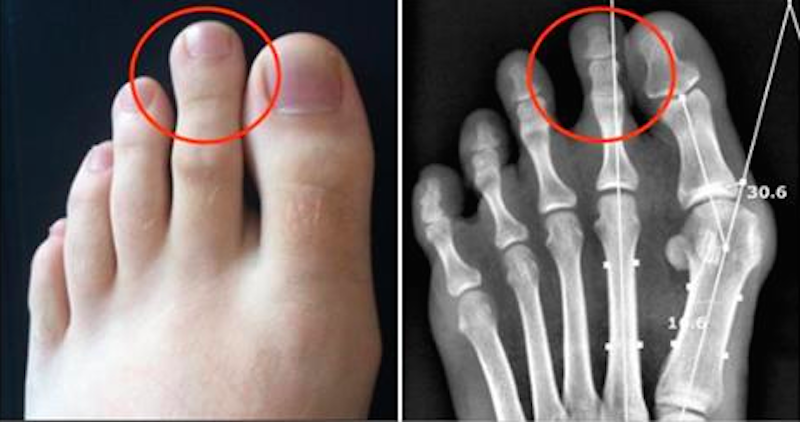

Al doilea deget

Oamenii cu al doilea deget mi lung tind să aibă calități de lider. Pot face pe șefii. Dacă degetul e mai mic, există o dorință pentru ordine și armonie.